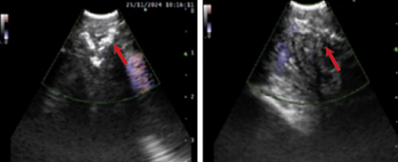

• 支气管镜:右中间支气管内侧壁向外凸起,黏膜充血肿胀,管腔显著变窄,腔内有脓性分泌物。

图2:患者支气管镜检查

术中,超声屏幕清晰地显示出7区淋巴结附近的多处高回声钙化病灶。在实时超声引导下,医生用高频针刀在支气管壁精准切开1厘米小口,黑色的钙化淋巴结随即暴露出来。借助异物钳,两枚压迫气道的钙化淋巴结被完整取出,再次超声确认无残留后,手术圆满完成。